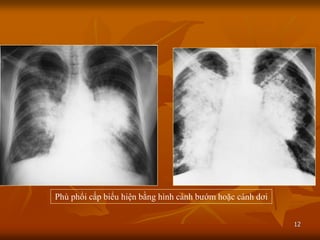

BUTTERFLY WINGS

(Pulmonary edema in a

patient with acute left

Phù phổi cấp biểu hiện bằng hình cánh bƣớm hoặc cánh dơi